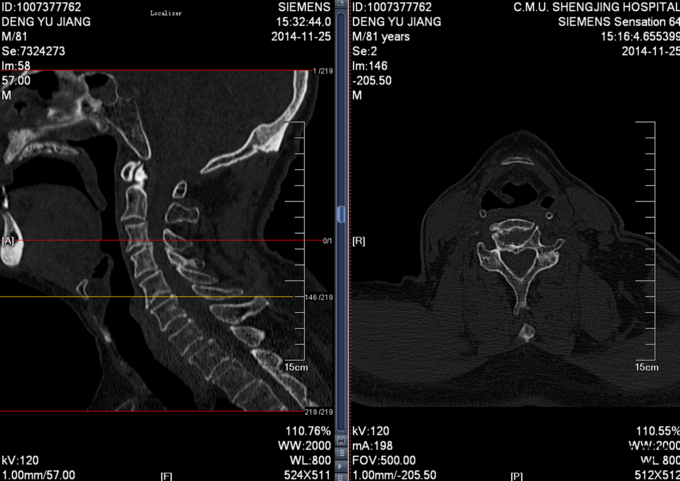

患者男,81岁,自述于1个月前出现双上肢感觉减退,发胀,以左侧为重,后来加重,左侧握力减退,于201医院就诊,行颈椎MR检查,提示为颈3-4、4-5间盘突出,为求进一步治疗就诊于我院,患者病来饮食、睡眠佳。大小便正常,体重无明显变化。

颈椎生理弯曲消失,活动度正常。双上肢感觉减退。双手握力(R5级,L4级),伸肘肌力(R5级,L5级),屈肘肌力(R5级,L5级),Hoffman(R-,L+)桡动脉搏动有力,末梢血运良。

诊断:颈椎病,颈椎间突出,高血压病 患者入院后完善相关检查,请相关科室及麻醉科会诊,医院医务部审批后,查无其他手术禁忌症,于全麻下行颈椎后路单开门椎管扩大减压侧块螺钉内固定术。术后给予患肢雾化祛痰,抗炎,消肿,营养神经,接骨等对症治疗。术后患者在颈领的保护下可下地行走,术后14天拆线后予以出院,